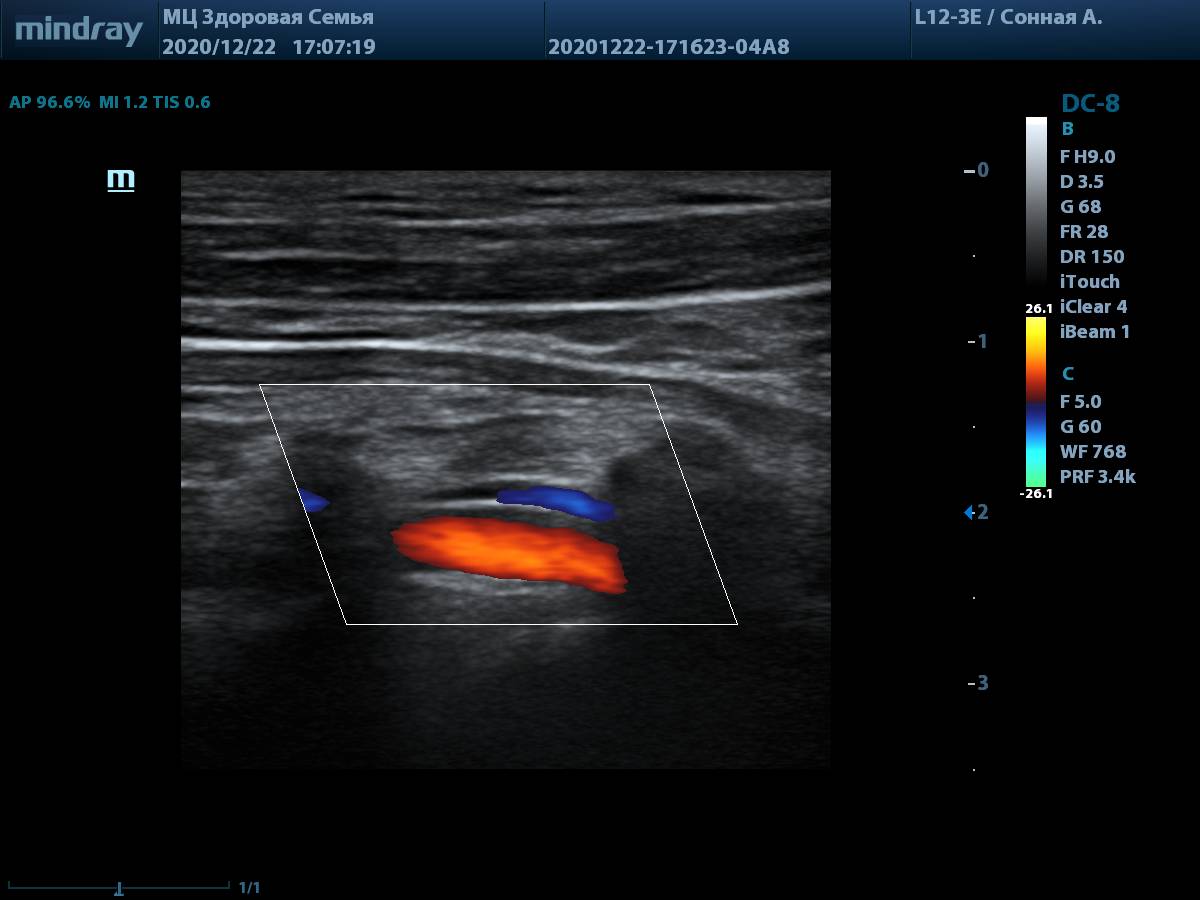

7. Линейный датчик L12-3E, оценка глубоких структур, таких как позвоночная артерия, не вызывает трудностей. Хорошая чувствительность цветового допплера на глубине.

8. Общая сонная артерия (L12-3E) с использованием системы автоматического измерения комплекса интима-медиа, согласно международным стандартам.